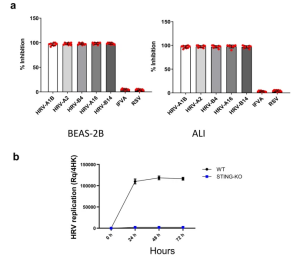

2.Validate the role of STING in the replication process of human rhinovirus

Human rhinovirus (HRV) is the most important pathogen that causes the common cold. The disease caused by this virus is a self limited disease, which generally heals itself in about one week. HRV belongs to the family of small RNA viruses. After infecting cells, it will reshape the internal and external membrane components of cells to form organelles that specifically promote virus replication. These organelles are called Replication organelles (ROS). Other single stranded positive RNA viruses also have this feature. STING is an important host factor of HRV infection. However, the function of STING in HRV replication cycle is still unclear. To verify the importance of STING for HRV replication, the authors used CRISPR/Cas9 technology to delete STING in BEAS-2B and primary human airway epithelial cells (ALI) cultured at the gas-liquid interface. The results showed that knockout of STING could significantly inhibit HRV replication, but had no significant effect on respiratory syncytial virus and influenza virus, indicating that HRV replication depended on STING [4].

Figure 4. STING is required for HRV replication